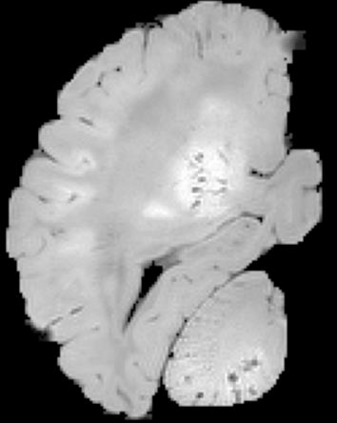

In neuroimaging, MRI tissue properties characterize underlying neurobiology, provide quantitative biomarkers for neurological disease detection and analysis, and can be used to synthesize arbitrary MRI contrasts. Estimating tissue properties from a single scan session using a protocol available on all clinical scanners promises to reduce scan time and cost, enable quantitative analysis in routine clinical scans and provide scan-independent biomarkers of disease. However, existing tissue properties estimation methods - most often $\mathbf{T_1}$ relaxation, $\mathbf{T_2^*}$ relaxation, and proton density ($\mathbf{PD}$) - require data from multiple scan sessions and cannot estimate all properties from a single clinically available MRI protocol such as the multiecho MRI scan. In addition, the widespread use of non-standard acquisition parameters across clinical imaging sites require estimation methods that can generalize across varying scanner parameters. However, existing learning methods are acquisition protocol specific and cannot estimate from heterogenous clinical data from different imaging sites. In this work we propose an unsupervised deep-learning strategy that employs MRI physics to estimate all three tissue properties from a single multiecho MRI scan session, and generalizes across varying acquisition parameters. The proposed strategy optimizes accurate synthesis of new MRI contrasts from estimated latent tissue properties, enabling unsupervised training, we also employ random acquisition parameters during training to achieve acquisition generalization. We provide the first demonstration of estimating all tissue properties from a single multiecho scan session. We demonstrate improved accuracy and generalizability for tissue property estimation and MRI synthesis.